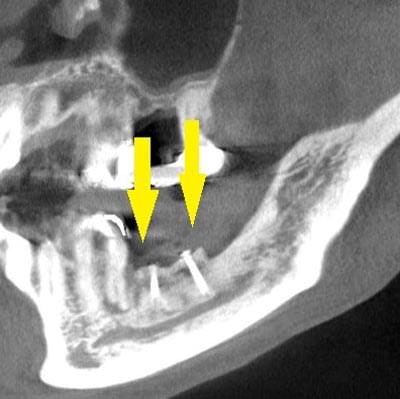

手術後の、別な方向からみたCT画像です。術前に大きく吸収されていた部分に、骨のブロックが移植され、骨が造成されています。真っ白にピンのように写るのは、骨を固定した小さなスクリューです。

移植した骨が周囲の骨と、結合したのを待ち、6か月後に、インプラント埋入手術を行いました。下の写真が、インプラント埋入後のCT画像で、黄色矢印に示すように、インプラントが2本埋入できました。

インプラント埋入後の、別な方向からみたCT画像です。神経の通る管にややギリギリでしたが、神経は傷つけずに、インプラントが埋入できました。この後、4か月ほどで、咬む歯の部分、上部構造を完成させました。